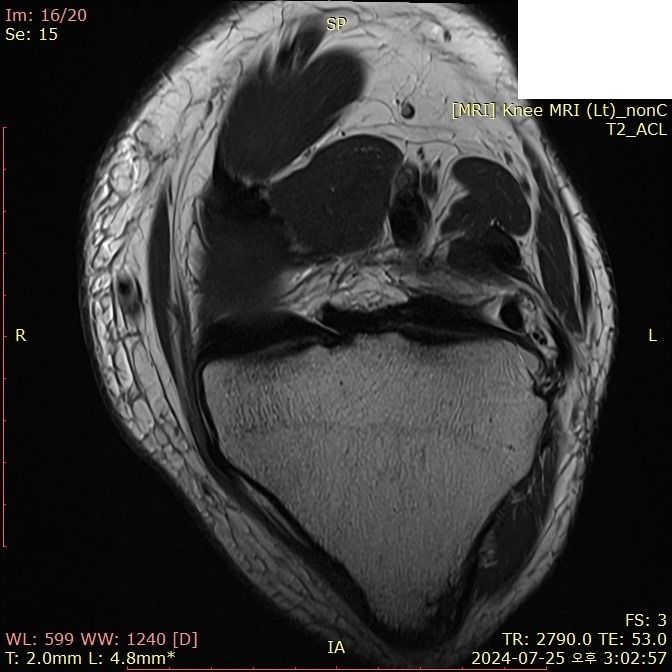

무릎 ACL(전방십자인대) 확인 부탁드려요

아스팔트에 무릎을 부딪쳐 심하게 부어서 mri 찍어봤는데 슬개골 비변위성 골절 판독 받은 건 기억 나는데, 인대는 기억이 잘 안나서 여쭤 봅니다..

전방십자인대 괜찮은가요...??ㅠㅠ